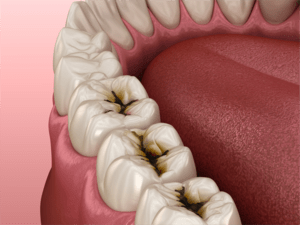

虫歯の見た目を写真で!

C1

黒い虫歯があるが、エナメル室内の浅い虫歯です。

C2

虫歯がエナメル質を超えて中まで進行しています。